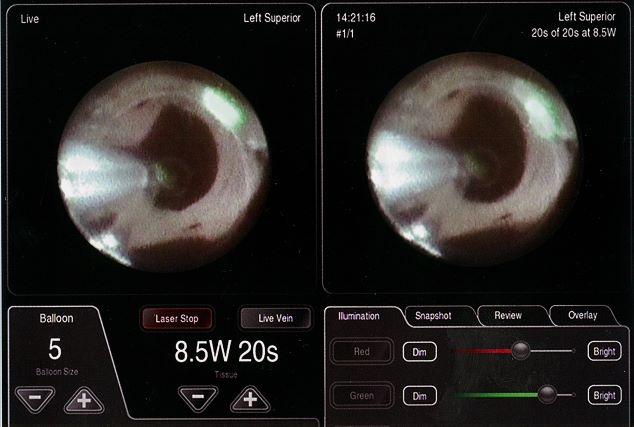

焼灼部位を可視化する

内視鏡を利用することで術者の「目」となり、焼灼部位をリアルタイムで可視化できます。心臓内部の直接的な指標を把握できることで、3Dマッピングを必要としない肺静脈隔離術が可能となりました。

レーザーエネルギーを操る

レーザーエネルギーとバルーンサイズの調整により、様々なシチュエーションに対応できます。バルーンを動かすことなくレーザー焦点調整を行えると共に、組織の厚さによってエネルギー量の調節が可能となりました。